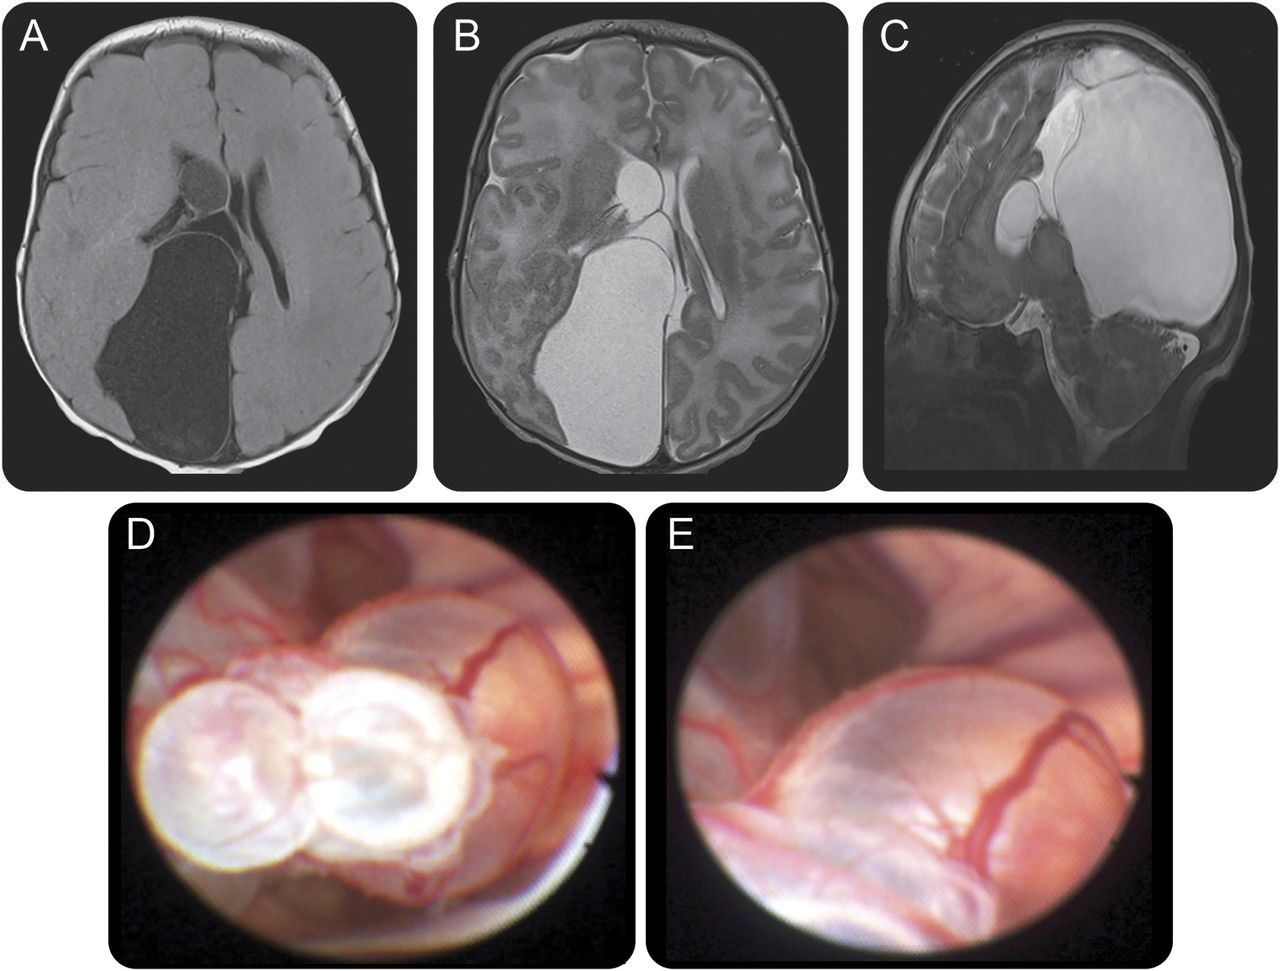

丽江的男性婴儿面对巨头和引起颅内压的迹象。体格检查,前囟门,膨胀,与头围增加紧张。MRI显示两半球间的multiloculated囊肿胼胝体发育不全(图中,得了)。病人接受正确的内镜第三脑室切开术脉络丛烧灼和内窥镜囊肿开窗术(图中,D和E)。两半球间的multiloculated囊肿与胼胝体发育不全是相对罕见的病变。1内窥镜下管理是一种微创的方法创建囊肿之间的通信,脑室系统和蛛网膜下腔从而避免永久性分流和显微手术。2

大脑核磁共振和围手术期内窥镜图像

轴向T1和t2加权(A, B)和矢状脑磁共振t2加权(C)展示了一个大型multiseptated两半球间的囊肿造成横向和第三ventriculomegaly。大后两半球间的囊肿会导致质量效应顶叶和枕叶,平坦和流离失所的外侧。注意胼胝体发育不全的。(D, E)围手术期内窥镜图像展示了多个在右侧侧脑室囊肿。